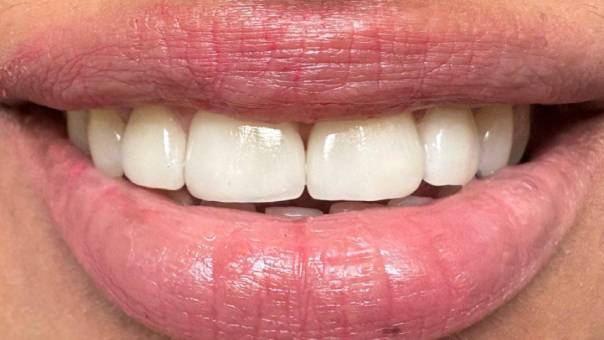

After tooth preparation for bridge

After Bridge placement

The transformation was remarkable. The reverse curve was corrected, alignment was improved, and the color and contour of the crowns blended perfectly with the surrounding teeth.

The patient was extremely satisfied with the outcome, expressing renewed confidence in their smile and improved comfort while biting and speaking.